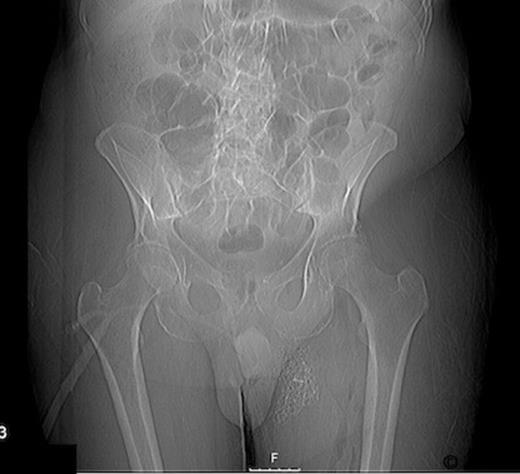

Radiographs confirmed subcutaneous gas associated with the swelling (figure 1). The patient was consented for incision and drainage of the collection, where it was noted that gas bubbles were released on initial stab incision. Copious grey watery fluid was drained from the cavity which appeared to track under the inguinal ligament. Cavity fluid and biopsy specimens were sent for microscopy, culture and sensitivity. The cavity was packed and broad spectrum antibiotics were started following consultation with a microbiologist. A pelvic CT scan with contrast was arranged (figure 2–4), which confirmed a vesicocutaneous fistula.